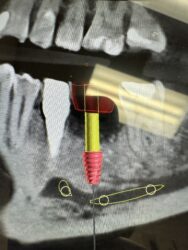

Hi everyone. The virtually planned implant #13 (3.8x12mm BH tapered pro) is considerably more submerged vs #12 implant (about 4mm difference). Would there be any serious long term issues with this large discrepancy between adjacent implant platforms? My initial thought is to GBR the buccal first so it would “fatten up” the thin crestal…

Rana and Jedediah -